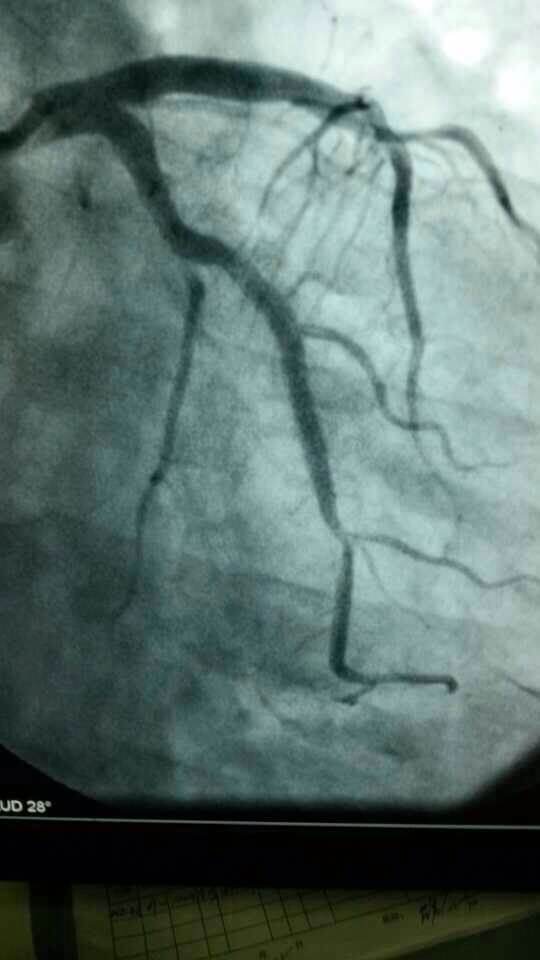

心脏有问题不可麻痹大意。急性胸痛的病人往往病情凶险,抢得时间就能挽救生命。今天,伦理片

心内科医务人员在崔勇主任的带领下,蔡亚滨、林福根、雷建林、陈明辉、何晓、李仲伟等抢救团队连续奋战 8个小时成功抢救3名心梗患者。虽然工作艰辛,但接诊的三位病人都能转危为安,对医生来讲是最大的安慰。